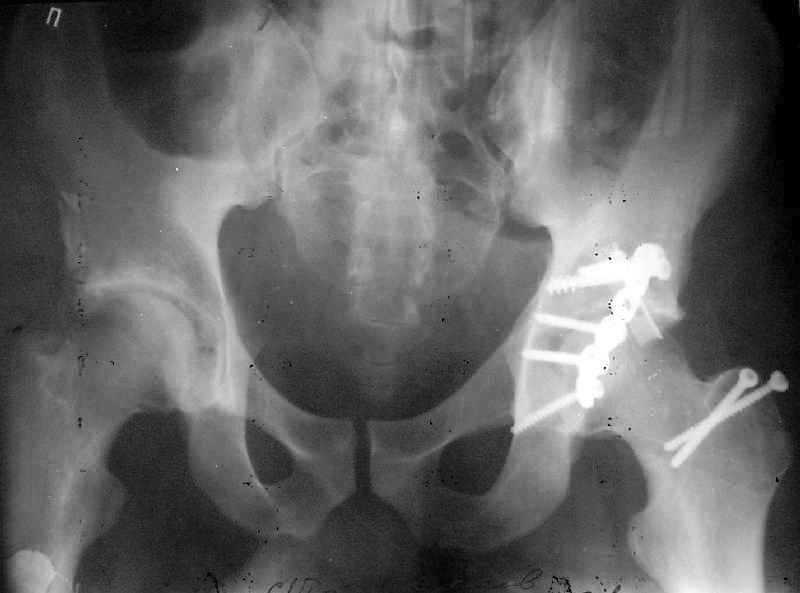

Пациент переведен в нашу клинику на 5 день после множественной травмы 25.01.2003 - двустороннее повреждение вертлужных впадин, разрыв левого крестцово-подвздошного сочленения. Вывихи обоих бедер. В месте первичного поступления подвздошный вывих правого бедра вправлен 26.01.2003, наложено вытяжение за левую вертельную область. Остеосинтез левой вертлужной впадины выполнен у нас 6.02.2003. Вопрос: надо ли синтезировать задне-верхний край правой вертлужной впадины?

правую впадину собрали здорово! Мои поздравления Рункову. Сами меня учили-учили, а где же запирательная проекция левой вертлужной

Поздравляю с отлично выполненой репозицией при остеосинтезе !